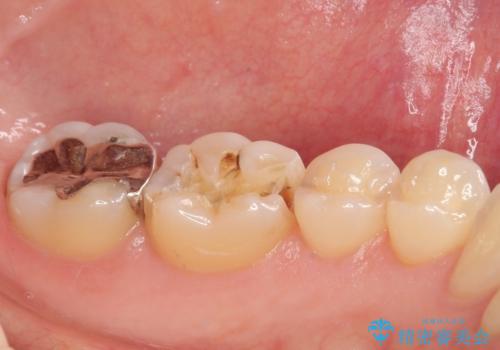

- 銀歯がとれたのでやり替えたいとのことで来院された患者様です。来院時特に症状もなく金属の詰め物(メタルインレー)がとれたのでセラミックの詰め物(セラミックインレー)にやり替えていくことになりました。また患者様のご希望によりひとつ後ろの歯の金属の詰め物(メタルインレー)のやり替えも同時に治療していくことになりました。

拡大鏡視野下で、金属の詰め物(メタルインレー)、保険のプラスチック、虫歯の除去を行い、セラミックインレーに適した形に整えました。